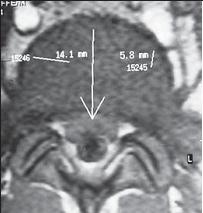

На МРТ № 13 наблюдается медиолатеральная грыжа межпозвонкового диска (заднебоковая) На МРТ № 14 наблюдается фораминальная грыжа межпозвонкового диска с локализацией внутрь межпозвонкового отверстия МРТ № 15 ![]() МРТ № 16

На МРТ № 15 наблюдается двухсторонняя экстрафораминальная грыжа межпозвонкового диска (расположенная за межпозвонковыми отверстиями) На МРТ № 16 наблюдается медиолатеральная протрузия и вентральная грыжа межпозвонкового диска